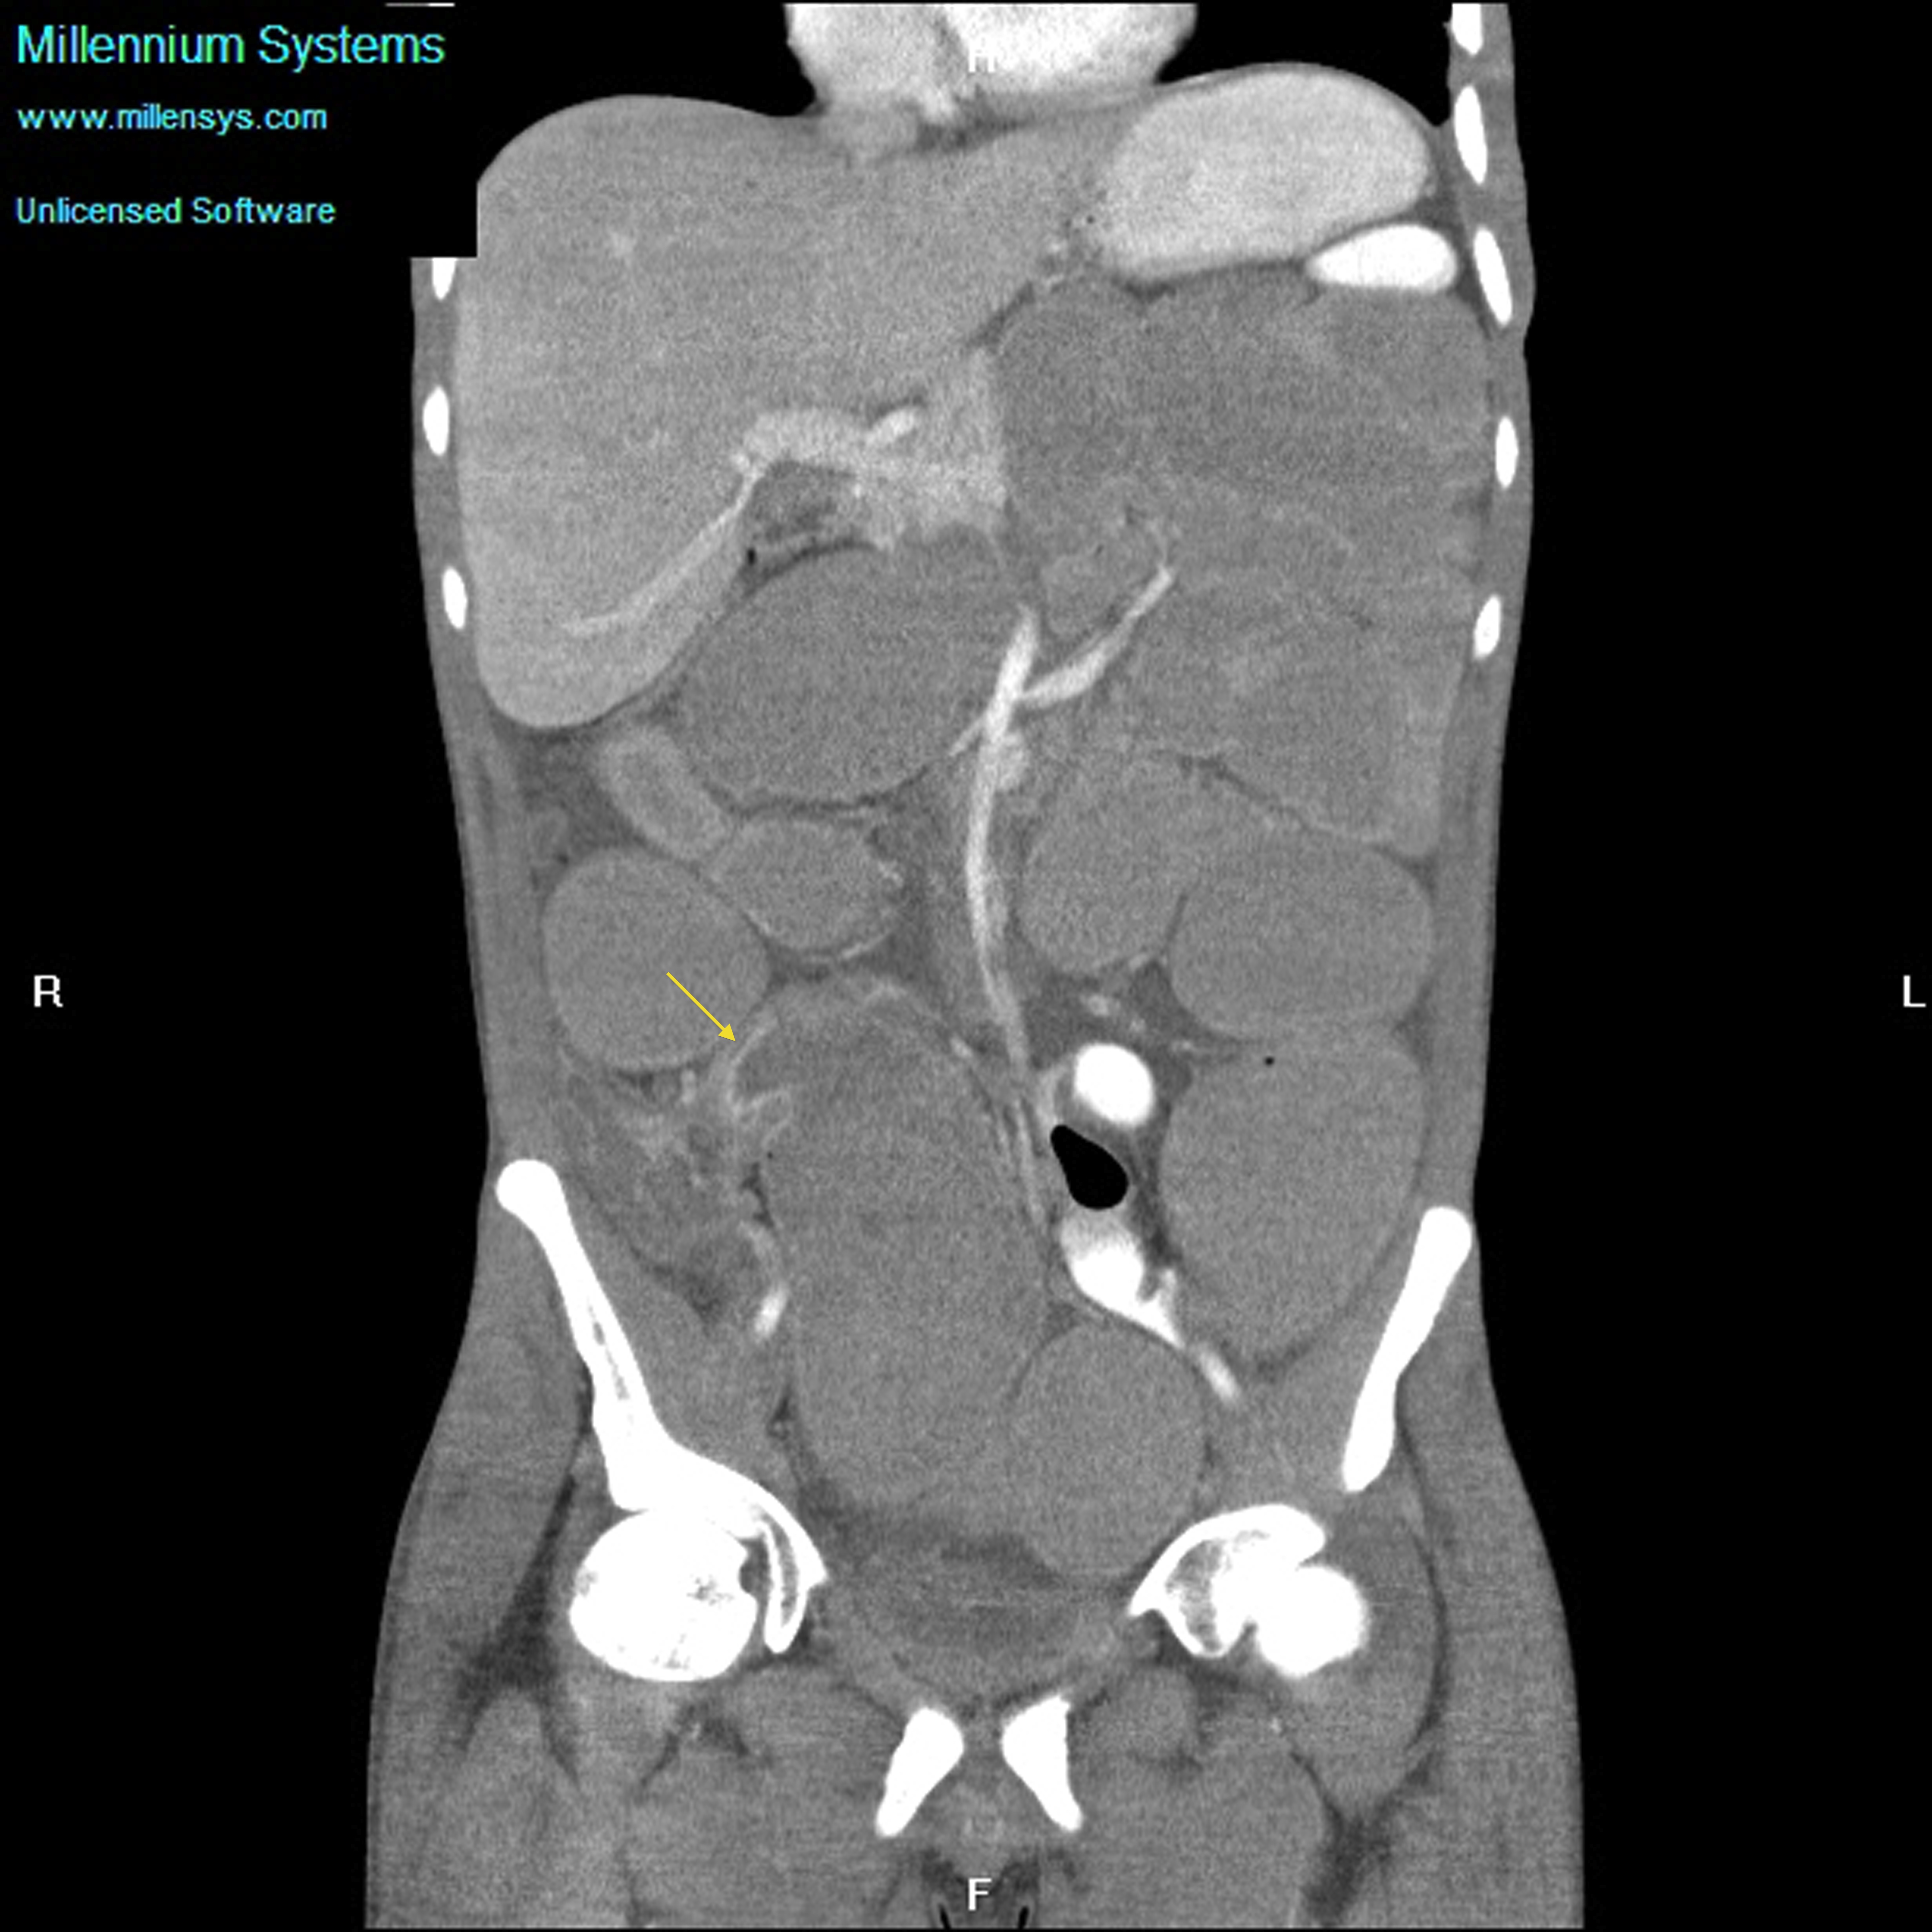

Small bowel obstruction is a common clinical presentation that presents a diagnostic conundrum. Over the last 2 decades, there has been a paradigm shift in the radiological investigation of small bowel obstruction (SBO) and in the indication for and timing of surgical intervention. Cross sectional imaging (predominantly computed tomography) has largely replaced the widespread use of radiographic small bowel follow-through studies as the imaging modality of choice for SBO. This article illustrates the current imaging modalities available for diagnosis of small bowel obstruction. (Full text available online at www.medpharm.tandfonline.com/ojfp) S Afr Fam Pract 2015; DOI: /10.1080/20786190.2014.977052